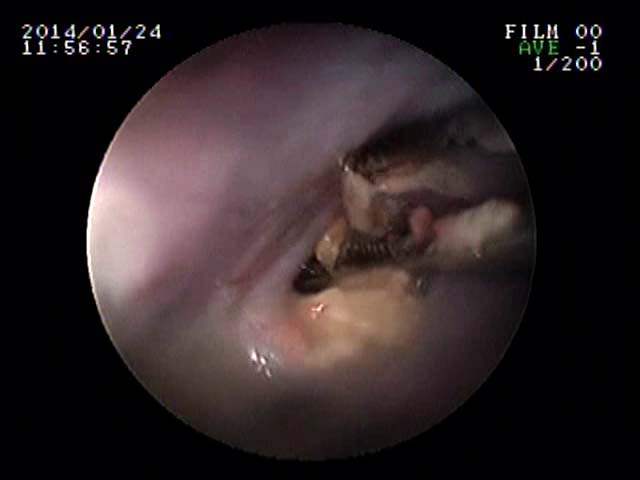

先日、2日前から食欲廃絶のチワワさんが来院しました。そのきっかけが、同居している大型犬のおやつを横取りしたときからとのことでした。話を聞いたら、その後からずっと泡状の液体を吐いているようでした。それは、おそらく唾液をのめなくて突出しているのだと直感しました。

ガムは仔牛のあばら骨ガムだったので、食道停滞を考えました。エックス線を撮影したら、さすがにあばら骨だけあってくっきり咽頭部付近の食道に写っていました。すぐに内視鏡をすすめて処置をはじめたのですが、扁平のガムが食道を拡張させはまり込んで内視鏡鉗子(直径2mm)ではとれませんでした。押して胃内に押し込むことも考えましたがびくともしません。そこで腹腔鏡(硬性鏡)用の鉗子(5mm)を内視鏡と併走させて食道の異物まで到達させ把持することを考え、実施したらなんとかうまくつかめました。場合によっては、開胸手術による食道切開で摘出することも適応になる症例であってもおかしくありませんでした。

これは、今までの経験が生かせた処置ともいえました。麻酔が覚めた本人はケロッとしていて、ごはんを欲しそうな様子でした。この顔をみたとき、ある意味充実感がありました。よかったね、富士ちゃん!

![]() |

食道にはまったガムを腹腔鏡鉗子で取り除いている様子 | 実際とれたあとの食道粘膜の写真(一部炎症とびらんがあります) | 正常の食道粘膜の写真 | 実際とれたあとの写真 (ガムの中にあばら骨があります) |